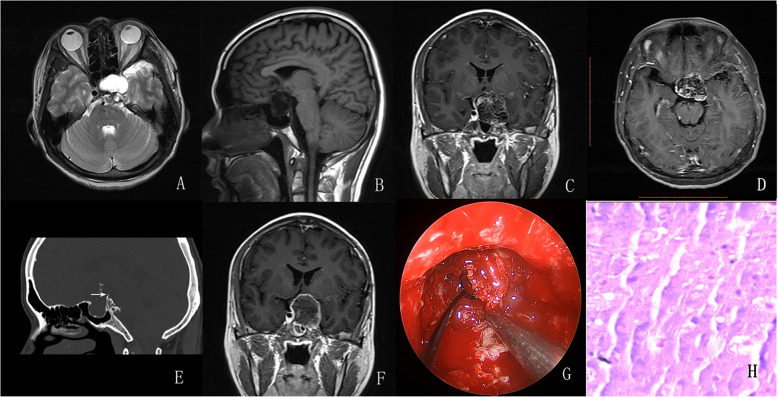

Conclusions: The preoperative diagnosis of sellar chondrosarcoma remains challenging and often requires differentiation from chordoma, INPA, or craniopharyngioma. When a calcified mass in the sellar region presents with intact or slightly disturbed anterior pituitary function, heterogeneous enhancement and no diffusion restriction on Magnetic Resonance Imaging(MRI) sequences, and surrounding bony destruction and bony attachment on Computed Tomography(CT) scans, a chondrosarcoma should be suspected preferentially. Complete resection is the optimal goal for the management of sellar chondrosarcoma, but adjuvant radiotherapy and periodic follow-up should be highlighted.